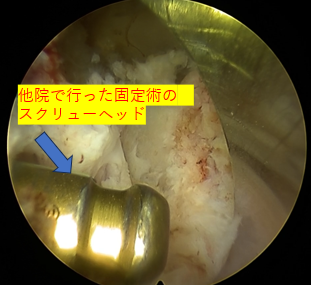

| 治療内容と方針 | 右下肢内側の痛み、しびれは後方固定除圧後の合併症である隣接椎間障害によるもので、右L4/5椎間孔の狭窄症が原因だったので「PEL(脊柱管狭窄症内視鏡下術)」を実施。神経を圧迫している骨をドリルで削開しました。削開後は、椎間孔狭窄の圧迫が取れて右L4神経根が確認できました。 それと同時に、神経修復作用の効果を期待できる血小板由来の成長因子を注入する「PRP療法」を行いました。 なお、他院で手術したL5/Sの部位は再発がないので、そこの部位の治療は行っていません。 |